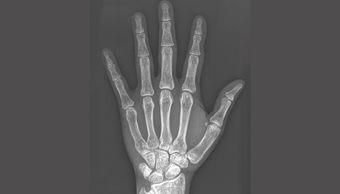

X線:からだの中を見る

レントゲンは皮膚を通して骨を見ることができる。